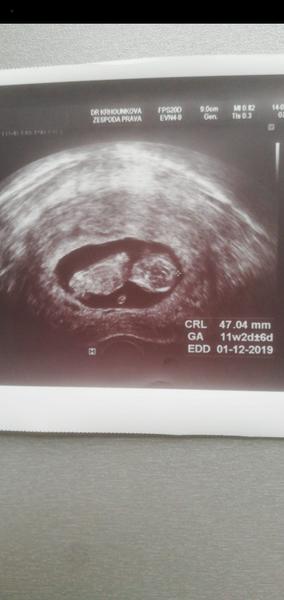

Ahoj holky, ta jsem se po X letech konečně poprvé zaregistrovala vždy jsem jen projížděl diskuze jako neaktivní člen, tak mam radost ze mohu byt konečně mezi Vami❤️jinak my mame termín 25.11-1.12 a jsme 11tt včera byla kontrola a odebrani krve na prvotrimestrální screening ktery nas čeká příští pátek, doktorka mi dokonce rekla i pohlaví což me trochu zarazilo, přiznám se ze jsem zadržovala slzy jelikoz jsem si přála vysněnou holčičku a na ultrz. Byl zvoneček 😄😄ale dnes jsem uz happy protože malej (4)bude mít bráchu a je to pro něj to nejlepší co může být ❤️